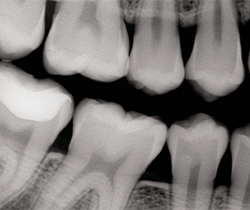

After occlusion is adjusted and restorations are finished and polished with OptraPol polishing cups and points (Ivoclar Vivadent), final radiographs and photos are taken to demonstrate the radiopacity of the material, the ideal interproximal contours and sealed margins, and its monolithic, void-free qualities (Figs. 16-20).

Fig. 20